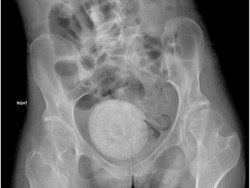

Batu Sebesar Jeruk Bersarang dalam Vagina Wanita Ini, Kok Bisa?

Seorang wanita mengalami kasus langka akibat batu vagina yang cukup besar bersarang di antara organ panggul. Wanita 27 tahun itu mengidap cerebral palsy spastik